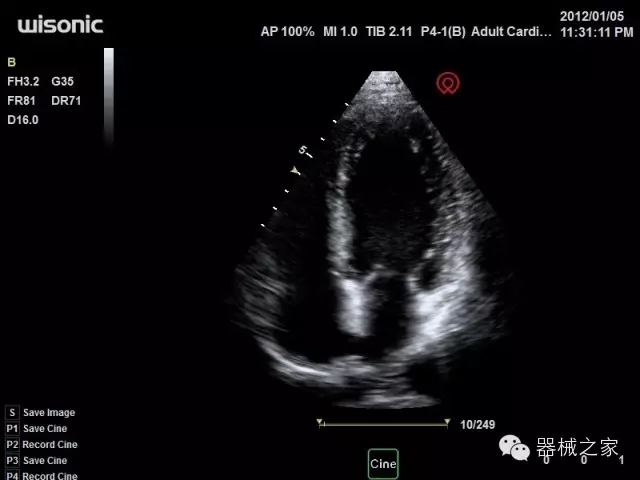

臨床圖片賞析

產(chǎn)品特點(diǎn)

·全球目前唯一一款配備主機(jī)雙探頭接口,整機(jī)重量(含電池)在5公斤以內(nèi)的便攜式彩超;

·一款互聯(lián)網(wǎng)彩超,只要有手機(jī)信號的地方就可以非常方便地實(shí)現(xiàn)遠(yuǎn)程會診和病案調(diào)取;

·獨(dú)有的HoloTM PW 實(shí)時3取樣門PW成像技術(shù),精確進(jìn)行血管診斷;